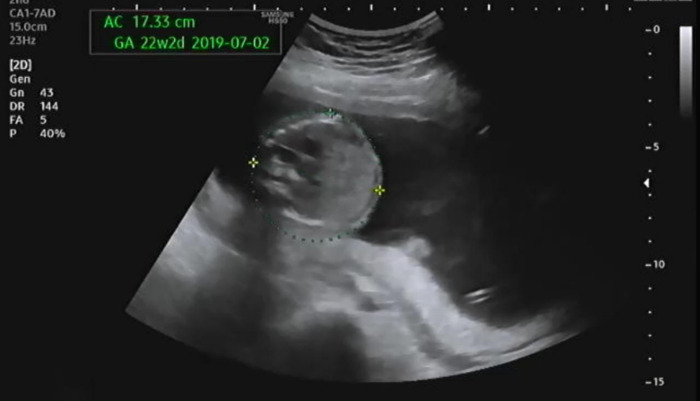

다음은 복부 둘레를 측정하는데 22주 2일 차로 해당되는 수치가 나와서 당황했다. 괜히 체중이 증가하는 나 때문에 아이의 복부 둘레도 증가하는 것은 아닌가 걱정이 되었다. 의사가 이 정도 차이는 괜찮다고 해서 걱정을 덜었다.